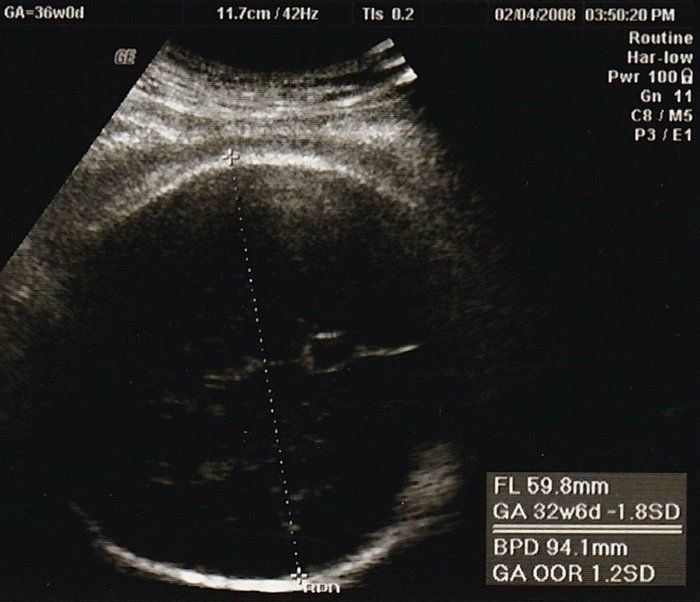

おなかの中はどうなっていくの? エコー写真で振り返る、高齢ママのはじめての妊娠生活 -

妊娠後期、赤ちゃんが育っていない? エコー写真で振り返る3人目の出産体験 -